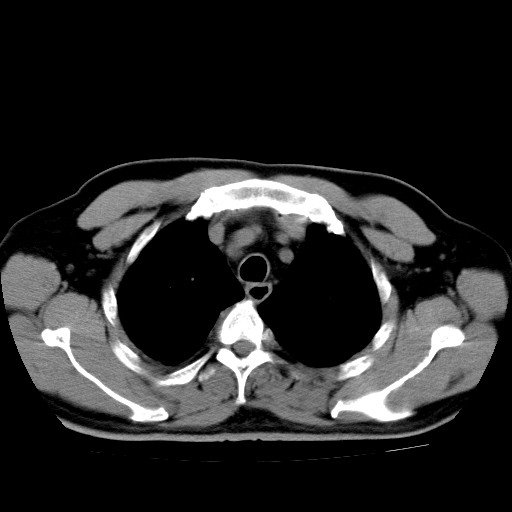

男,54岁,咳嗽,右侧胸痛10天。肺窗>150k,传不了

右肺中心型肺癌并右下肺不张,右侧胸膜纵隔转移。

右中央型肺癌并右肺下叶不张,纵隔内及右胸膜转移,右胸腔积液

考虑   右肺癌伴右下肺部分不张,阻塞性肺炎,纵隔淋巴结增大,右侧胸腔积液其他待排

考虑右肺下叶中央型肺癌并右肺下叶不张,纵隔淋巴结内及右胸膜转移。建议增强。

右下叶大片实变,肺门未见明显肿块影。有胸腔积液和纵隔内肿大淋巴结影。没有增强和肺窗,不好定。

考虑:1、右下叶周围型肺癌伴胸膜、纵隔淋巴转移?

右下叶大片性阻塞性肺炎,肺门未见明显肿块影,纵隔内可见肿大淋巴结影,右见右侧胸腔积液及右侧胸膜增厚。

考虑:右侧中心性肺癌?伴纵隔淋巴结转移。建议上传肺窗。